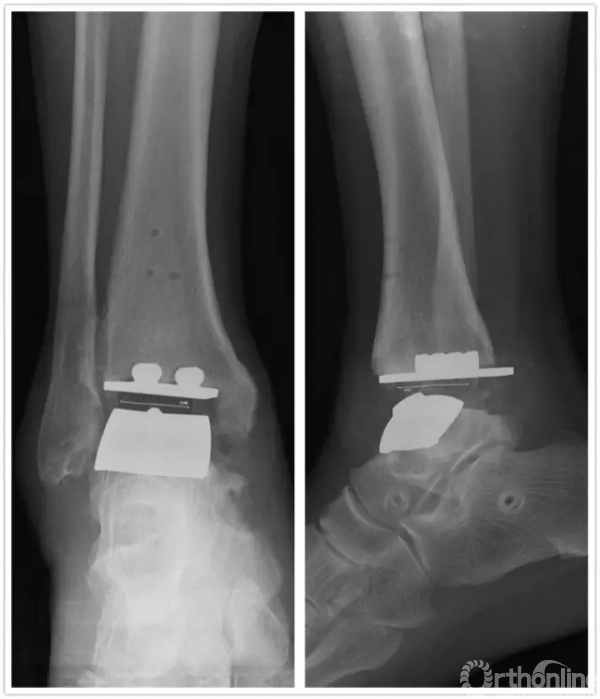

直到1年前,方老伯感觉右侧踝关节又开始出现肿胀疼痛,劳作后加重,最近越来越重。20167月再来徐主任门诊复查,徐主任考虑踝关节假体出现了松动,距骨有了塌陷,关节力线有所偏移。鉴于目前瑞金医院足踝外科已经开展踝关节INBONE假体置换术,积累了一定的经验,于是徐主任向患者及家属解释病情,建议再行踝关节翻修术。

手术中首先沿原手术切口进入,保护神经血管肌腱组织,清理踝关节假体周围骨赘,取出原关节假体,将患足置于专门的定制支架中,在透视下反复调整足踝及导针位置,力求最高精确度。在导板的定位下进行胫骨远端和距骨截骨,试样假体大小,置入合适匹配的踝关节假体及垫片完成全踝关节假体的置换,然后再行距下关节融合术。历经4小时,手术过程非常顺利,术后患者恢复良好,手术取得圆满成功。